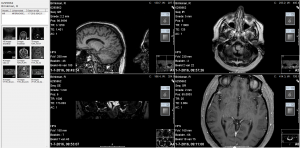

Vandaag 13 juli bij neuroloog Engström in het MCL te Leeuwarden geweest voor de uitslagen van het ENG onderzoek en de MRI scan.

Vandaag 13 juli bij neuroloog Engström in het MCL te Leeuwarden geweest voor de uitslagen van het ENG onderzoek en de MRI scan.

13 juli 2016

Vandaag 13 juli bij neuroloog Engström in het MCL te Leeuwarden geweest voor de uitslagen van het ENG onderzoek en de MRI scan.

Vandaag 13 juli bij neuroloog Engström in het MCL te Leeuwarden geweest voor de uitslagen van het ENG onderzoek en de MRI scan.Gebleken is dat mijn linker gehoororgaan ten opzichte van het rechter gehoororgaan wederom slechter is geworden. Het is met 42% toegenomen.. Er bevinden ook nog steeds kristallen in mijn gehoorzakje. Deze kunnen door de Epley manoeuvre weer hersteld worden, maar die heb ik al zo vaak gedaan en niets heeft geholpen. Bij de MRI scan zijn geen noemenswaardige afwijkingen gevonden. In ieder geval geen Brughoek tumor. Ik heb de scan op het scherm bekeken en zag duidelijk dat er nog vele goed gevulde verstand elementen aanwezig zijn.

Vandaag 1 juli naar het MCL te Leeuwarden geweest voor een MRI scan van het hoofd. Het is toch weer even wennen als je zo’n apparaat ziet en er in moet. Bij de vorige keer lag ik iets schever en kon zodoende uit het apparaat naar buiten kijken. Nu lag ik platter en zag alleen het binnenwerk. Ik ging met geopende ogen naar binnen en kreeg meteen een claustrofobie aanval. Paniek! Haal mij er onmiddellijk weer uit. Zo gevraagd zo gedaan. Even op adem komen. Ik was ook duizelig. Toch maar weer opnieuw proberen en nu maar met de ogen dicht. Gelukkig dat werkte. En na veel en afwisselend langdurig lawaai van het apparaat zat de eerste ronde erop. Ik kreeg vervolgens een vloeistof ingespoten zodat ze de hersens (als ik die tenminste heb) beter kunnen zien van binnen. Ogen dicht en deze keer duurde het maar drie minuten. Een beetje dronken liep ik de behandelkamer uit op zoek naar mijn vrouw en een lekker bakje koffie.

Vandaag 1 juli naar het MCL te Leeuwarden geweest voor een MRI scan van het hoofd. Het is toch weer even wennen als je zo’n apparaat ziet en er in moet. Bij de vorige keer lag ik iets schever en kon zodoende uit het apparaat naar buiten kijken. Nu lag ik platter en zag alleen het binnenwerk. Ik ging met geopende ogen naar binnen en kreeg meteen een claustrofobie aanval. Paniek! Haal mij er onmiddellijk weer uit. Zo gevraagd zo gedaan. Even op adem komen. Ik was ook duizelig. Toch maar weer opnieuw proberen en nu maar met de ogen dicht. Gelukkig dat werkte. En na veel en afwisselend langdurig lawaai van het apparaat zat de eerste ronde erop. Ik kreeg vervolgens een vloeistof ingespoten zodat ze de hersens (als ik die tenminste heb) beter kunnen zien van binnen. Ogen dicht en deze keer duurde het maar drie minuten. Een beetje dronken liep ik de behandelkamer uit op zoek naar mijn vrouw en een lekker bakje koffie.Nu maar afwachten wat het resultaat van deze scan is. Op 13 juli heb ik weer een afspraak met de Neuroloog.